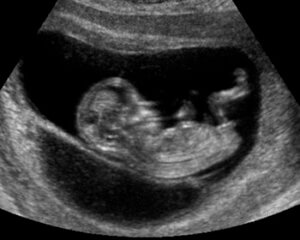

Once you have conceived, Progesterone is needed to strengthen the uterine lining so it remains strong enough to hold the pregnancy until the placenta kicks in at the end of the first trimester, between 6-10 weeks. Normally during pregnancy a woman’s body naturally starts to produce more progesterone to cover this function. However, sometimes not enough is produced, sometimes no extra progesterone is produced and sometimes it’s just not as effective as it needs to be. This means that the uterine lining breaks down and the pregnancy results in a miscarriage.

If you have suffered from more than 1 early miscarriage, a good treatment option would be to use a natural progesterone replacement therapy. Progesterone treatments help the body to maintain sufficient levels throughout the conception and pregnancy and can therefore help conception and see your pregnancy along to full term.